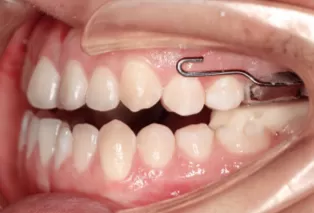

Intraoral photos